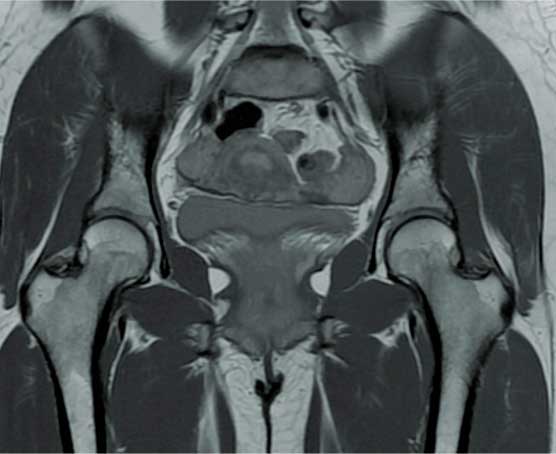

Artroscopia

de cadera

Cirugía mínima invasiva que se realiza haciendo tres puertos alrededor de la cadera por los cuales se introduce una cámara y observamos el interior de la articulación para buscar el daño o problema, también se introducen instrumentos con los cuales se permiten reparar las lesiones.

¿Por qué se realiza?

Está indicada en un paciente adulto joven para diagnosticar y tratar con certeza problemas de bloqueo en la cadera, extracción de cuerpos libres intrarticulares, rupturas de labrum, lesiones del cartílago y choque femoroacetabular.